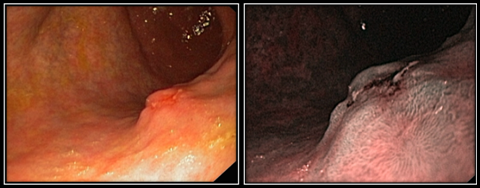

Инфильтративная форма НЭО желудка выявлена у 5 пациентов. Определяется в виде инфильтративного или инфильтративно-язвенного образования с выраженным подслизистым компонентом опухолевой инфильтрации, определяющимся в виде конвергенции утолщенных плотных складок (рис. 3а). Также отмечается нарушение перистальтической волны в зоне образования. При осмотре с оптическим увеличением в режиме NBI отмечается нарушение архитектоники слизистой оболочки в виде нарушения регулярности ямочного рисунка вплоть до аморфной структуры (полное отсутствие ямочного рисунка см. на рис. 3б). Архитектоника сосудистого рисунка в зоне образования изменена — нарушена регулярность строения сосудистого рисунка, отмечается его стертость, прослеживаются прерывистые извитые микрососуды.

Рис. 3 (а, б). Эндофото. Инфильтративная форма НЭО желудка